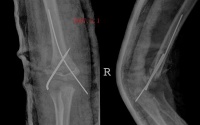

,烧伤或破伤风病人。外伤后,软组织内出血可能是造成骨化的原因。常于外伤2-3周后,在软组织出现钙化及骨化。病变常出现在易接受外伤的部位,如肘、股、臀部。在邻近长骨的骨干部分沿骨干的方向排列,呈层状骨化,而且于一处或数处可与邻近骨相联。病变很少伸延到骨端及关节的部位。

骨化好发与肱前肌,表现为肘关节区肿胀与疼痛,肘关节被动与主动活动均受限。疼痛与肿胀减退后在肘关节前方可以摸到一个界线清楚的硬的肿块。因肌肉无弹性,故肘关节伸屈受限;由于肿块的阻挡,屈曲也明显受限。

x线特征:受伤后不久可出现局限性肿快。伤后3-4周,在肿快内显示毛状致密象,其临近骨将显示骨膜反应。伤后6-8周,病变边缘部清楚地被致密骨质所包绕,而具有新生骨的外貌。软组织肿块的核心部有时显囊性变且逐渐扩大其内腔,到晚期而显出类似蛋壳状的囊肿。伤后5-6个月肿块收缩,因而肿块与邻近的骨皮质和骨膜反应之间显出x线透亮带。